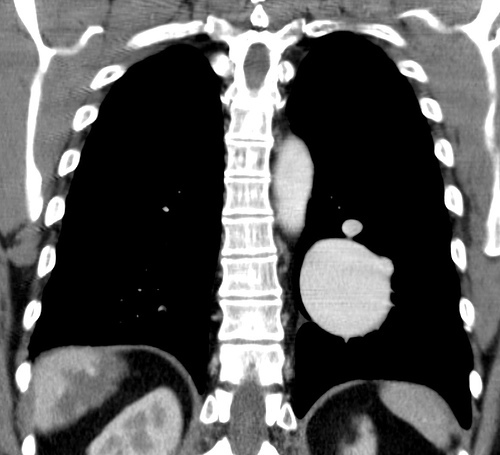

There is a well defined, brilliantly enhancing round lesion is noted in the left lung suggestive of pulmonary arteriovenous malformation.

Incidentally noted a large haemangioma is the superior segments of liver.

Imaging features are most likely suggestive of Osler-Weber-Rendu syndrome.

Hereditary haemorrhagic telangiectasia (HHT), also known as Osler-Weber-Rendu syndrome, is a rare inherited disorder characterised by abnormal blood vessel formation in the skin, mucous membranes, and organs including the lungs, liver, and central nervous system.

pulmonary: 20%pulmonary arterio-venous malformations (AVMs)

36% of patients with solitary pulmonary AVM have HHT

57% of patients with multiple pulmonary AVMs have HHT

chest x-ray: well-circumscribed mass (may be lobulated) with enlarged draining vein

CT: well-circumscribed vascular mass with enhancing feeding artery and draining vein